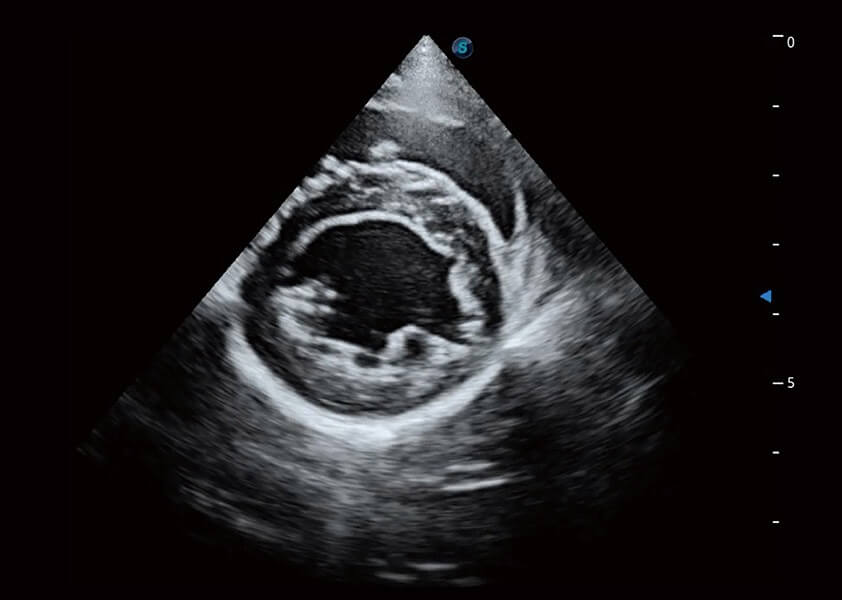

ProPet 60 作為一款高端臺(tái)式動(dòng)物超聲設(shè)備,為動(dòng)物醫(yī)生的日常診斷提供了一系列貼合動(dòng)物臨床需求、解決臨床實(shí)際問(wèn)題的高級(jí)成像功能。憑借全系列高清探頭,滿(mǎn)足醫(yī)生對(duì)腹部、心臟、生殖、淺表、肌骨等成像的所有需求,切實(shí)幫助您提升檢查效率,提高診斷信心。